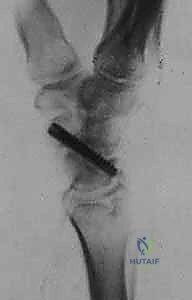

- التخدير والتحضير: تتم العملية غالباً تحت تخدير موضعي (Block) للذراع أو تخدير عام. يتم استخدام عاصبة (Tourniquet) لمنع تدفق الدم مؤقتاً لضمان رؤية جراحية واضحة تماماً.

- الشق الجراحي: يقوم الدكتور هطيف بعمل شق جراحي صغير ودقيق (حوالي 3-4 سم) في الجهة الظهرية أو الراحية للرسغ، مع مراعاة الحفاظ على الأعصاب الحسية والأوتار المحيطة.

- الوصول إلى العظم الزورقي: يتم فتح كبسولة المفصل بحذر شديد للوصول إلى العظم الزورقي التالف.

- الاستئصال الدقيق: باستخدام أدوات جراحية ميكروسكوبية دقيقة، يتم استئصال حوالي 3 إلى 4 مليمترات من القطب البعيد للعظم الزورقي. هذه الكمية كافية لمنع الاحتكاك مع عظم الكعبرة، وفي نفس الوقت تحافظ على استقرار الأربطة.

- تقييم المفصل: يتم فحص باقي عظام الرسغ للتأكد من عدم وجود خشونة متقدمة في أماكن أخرى.

- الإغلاق والخياطة: تُغلق كبسولة المفصل والجلد بخيوط تجميلية دقيقة لتقليل الندبات، ثم يُوضع الرسغ في جبيرة داعمة.